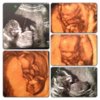

juz oficjalnie- bedzie chlopak

Pan Tadeusz (aka Soplica orzechowa lol)

ma 10.3cm lub 11cm (dwa rozne opisy wiec nie wiem w koncu)

gine powiedziala ze juz glowna i twarzyczka jest ladnie uksztaltowana no i widac bylo jajeczka nie do pomylenia

no i na koniec ladnie nam pomachal